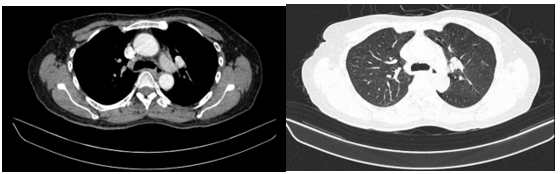

Hình ảnh chụp cắt lớp vi tính ngực: Dải xẹp phổi rải rác thuỳ dưới hai phổi. Nhu mô còn lại đồng nhất, không thấy tổn thương khu trú hoặc lan tỏa. Không thấy tổn thương hình mờ dạng lưới. Không thấy giãn phế quản – phế nang.

Hình 6. Phim chụp cắt lớp vi tính chưa phát hiện tổn thương thứ phát.

Chụp cắt lớp vi tính bụng - tiểu khung: Hình ảnh giãn đường mật trong gan phải/Sonde dẫn lưu đường mật gan phải - Gan trái đã cắt.

Hình 7. Phim chụp cắt lớp vi tính vụng cho thấy phần gan trái đã cắt (hình mũi tên)- Sonde dẫn lưu đường mật gan phải( vòng tròn đỏ).